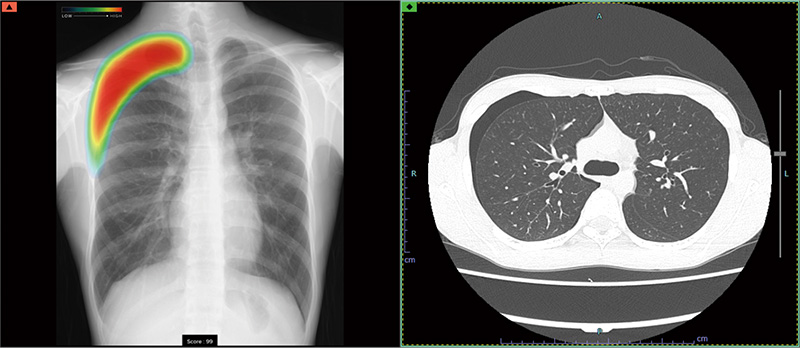

症例別ヒートマップとCTの例

当院では、富士フイルム社製の最新AI技術を搭載した画像診断ワークステーション「CarnaCore(カルナコア)」を導入しています。

このシステムでは、AIが撮影画像を瞬時に解析します。肺がんの疑いがある結節、肺炎、気胸といった見落としがちな微細なサインを自動検出し、医師の診断を強力にバックアップします。

医師による確かな読影に、客観的なAI解析を組み合わせることで、病変の早期発見と診断精度の向上に努め、より安心で効率的な診療体制を提供いたします。

• 高精度な解析: AI技術(Deep Learning)が医師の画像診断を強力にバックアップ。